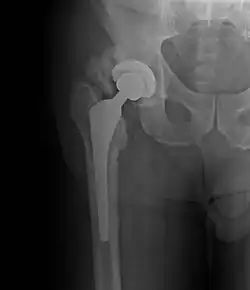

A ossificação heterotópica é comum após trauma físico grave, especialmente quando envolve lesão medular, e em vários tipos de cirurgia ortopédicas. Alguns casos só são perceptíveis com um exame de raio X enquanto os mais graves podem causar deformações sérias, dor e incapacitar certos movimentos.[3]

O tratamento geralmente envolve cirurgia para reposicionar o(s) órgão(s) ou osso(s) afetado(s), utilização prótese e longos períodos de fisioterapia. Alguns medicamentos típicos de pós-cirúrgicos como antibióticos e anti-inflamatórios podem ser usados para evitar complicações e analgésico pode ser prescrito para diminuir a dor.